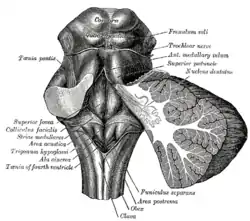

Hind- and mid-brains; postero-lateral view.

Hind- and mid-brains; postero-lateral view. Figure showing the mode of innervation of the Recti medialis and lateralis of the eye.